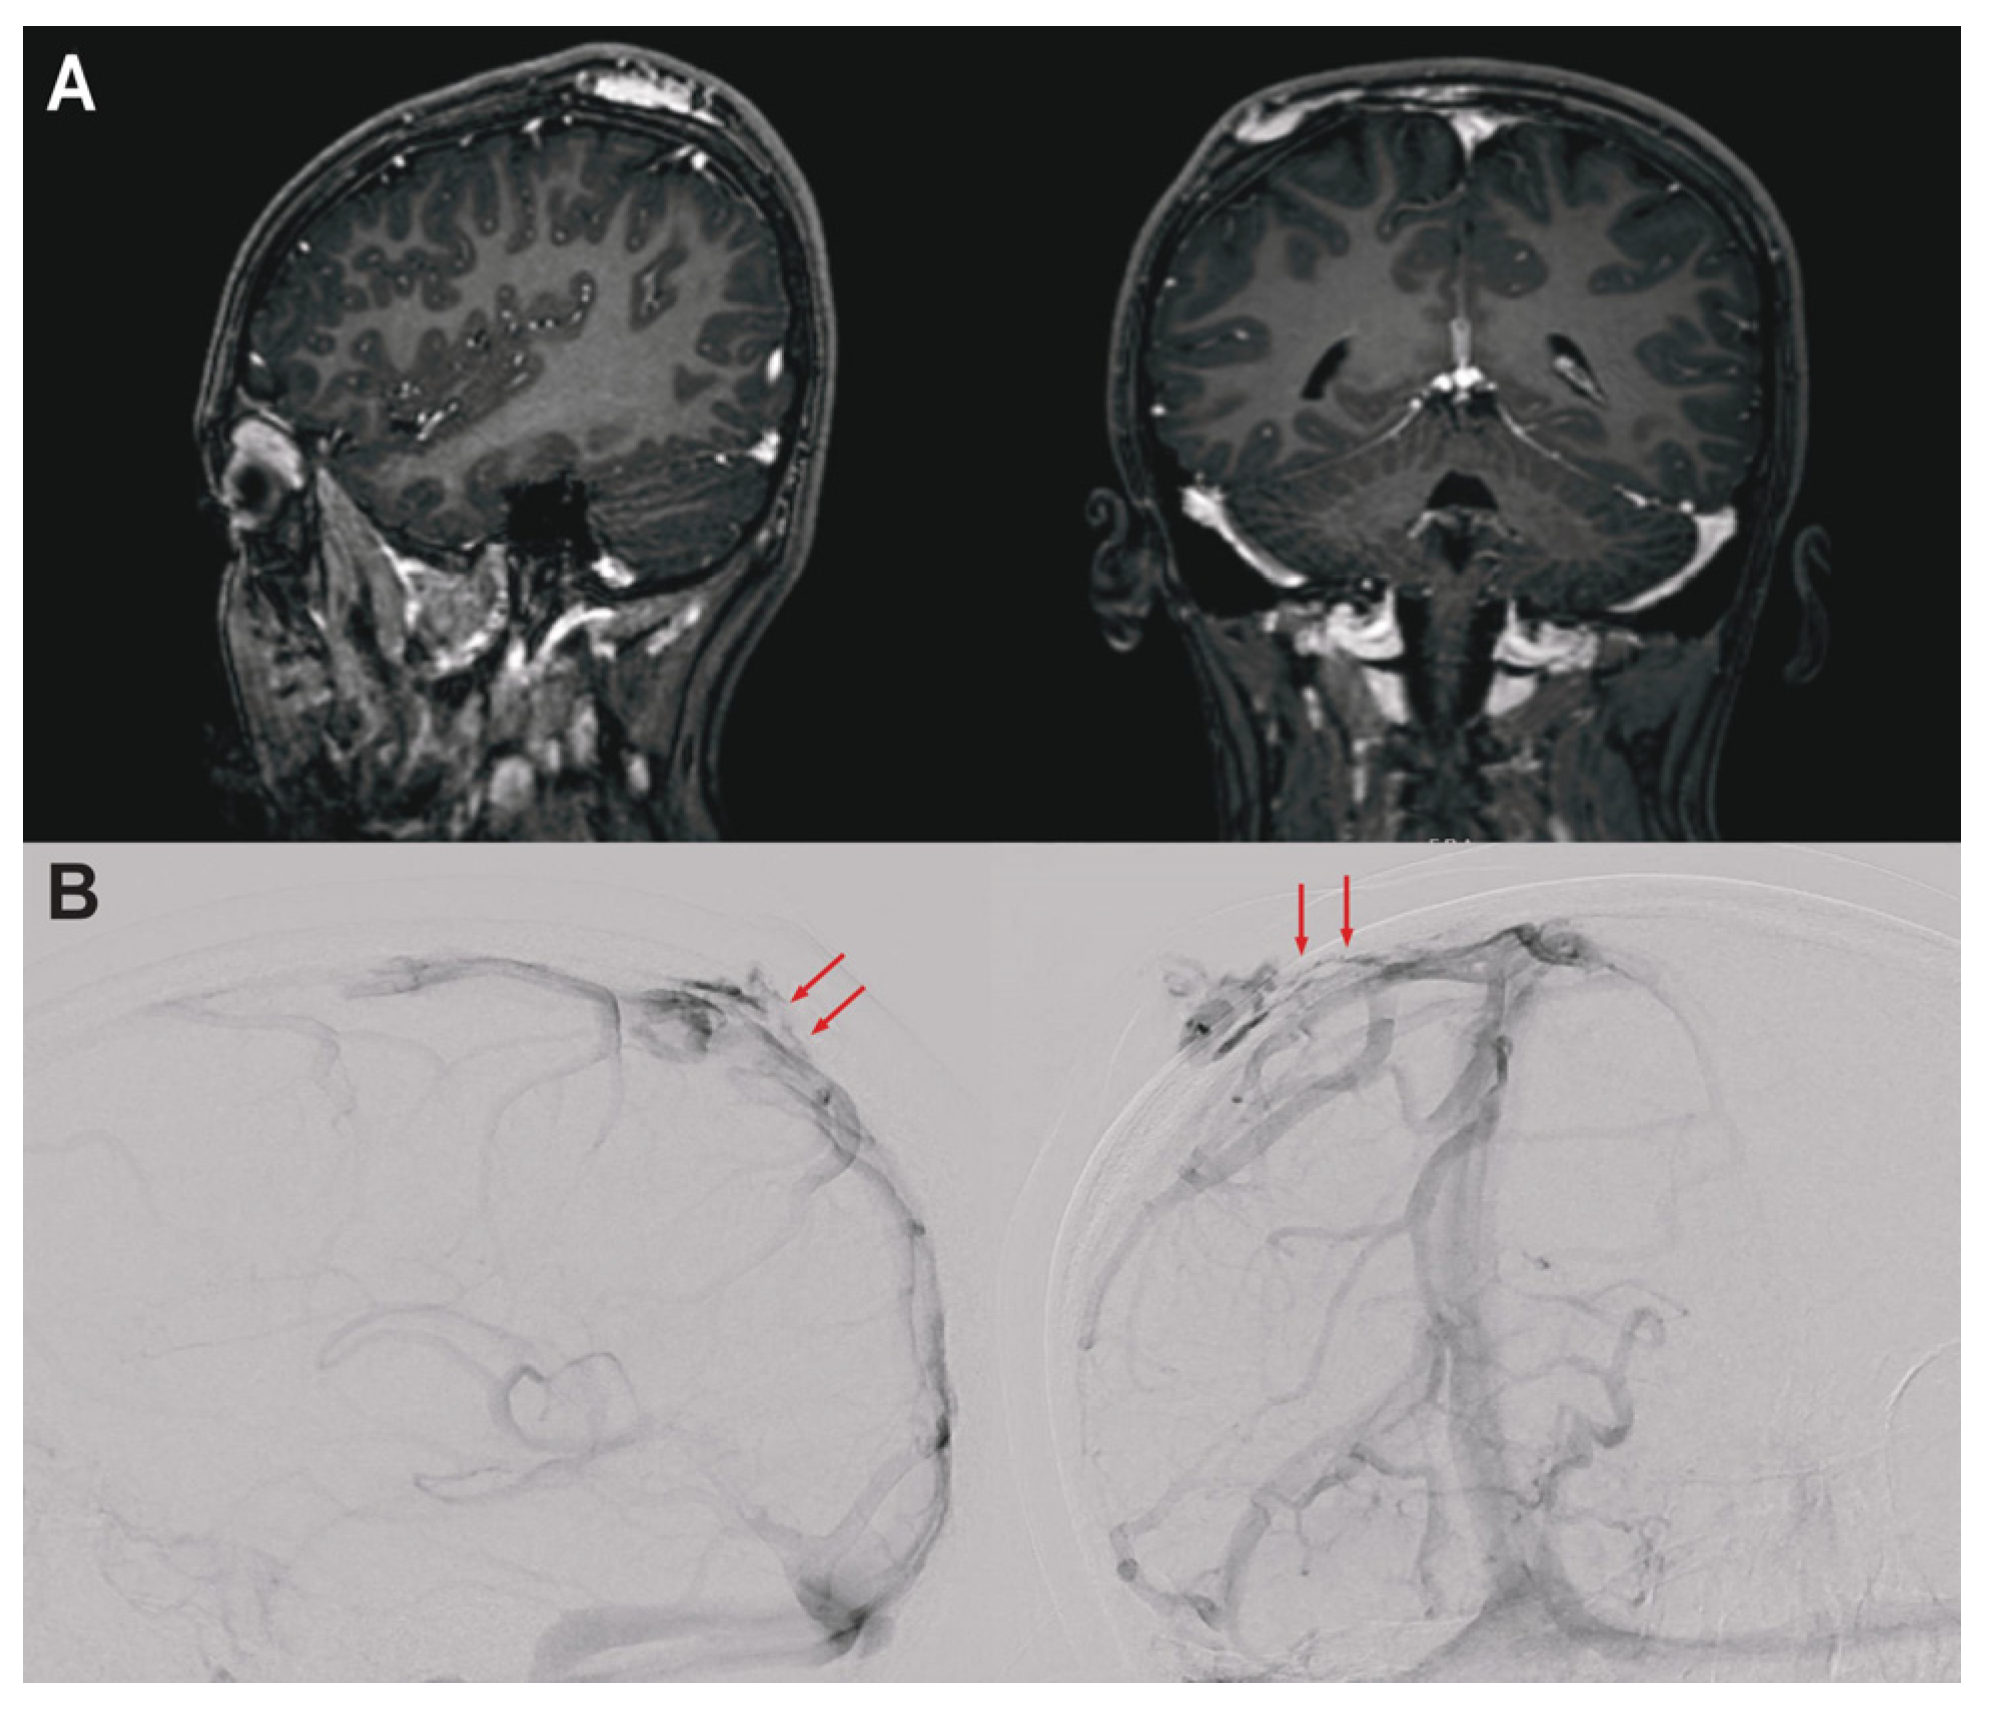

3.1. Clinical Presentation